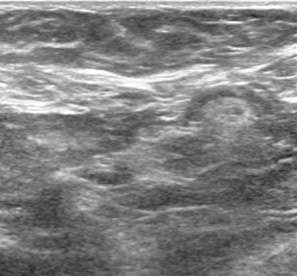

Ultrasound is the primary imaging modality used in the evaluation of lumps outside of the breast or in patients who are less than 30 years of age.2 On ultrasound, accessory breast tissue appears like breast tissue within the main pectoral breast – a mixture of fibroglandular tissue and lobules of fat (Fig. 2).

Case: Accessory  Breast Tissue Figure 2

Figure 2: Ultrasound shows dermis, lobules of fat, and accessory breast tissue indicated by A, B, and C, respectively. An incidental lymph node is seen.